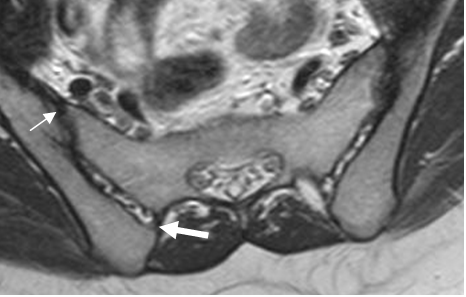

Fig 2. Ligamentos normales de articulación sacroiliaca.

RM axial en T1. Ligamentos sacroiliaco anterior (Flecha delgada) y posterior (Flecha gruesa).